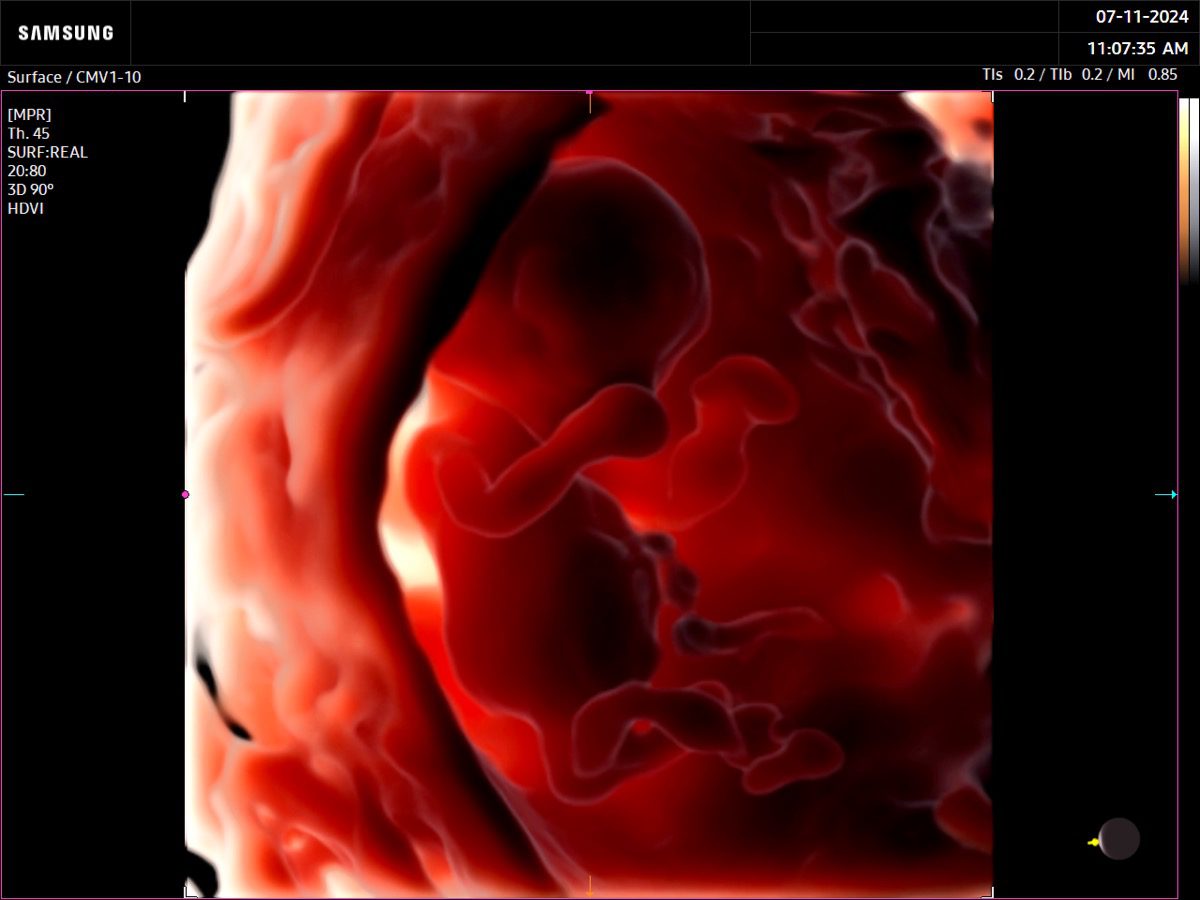

Comprehensive, advanced and expert MFM care for high-risk pregnancies

- Fetal anomalies